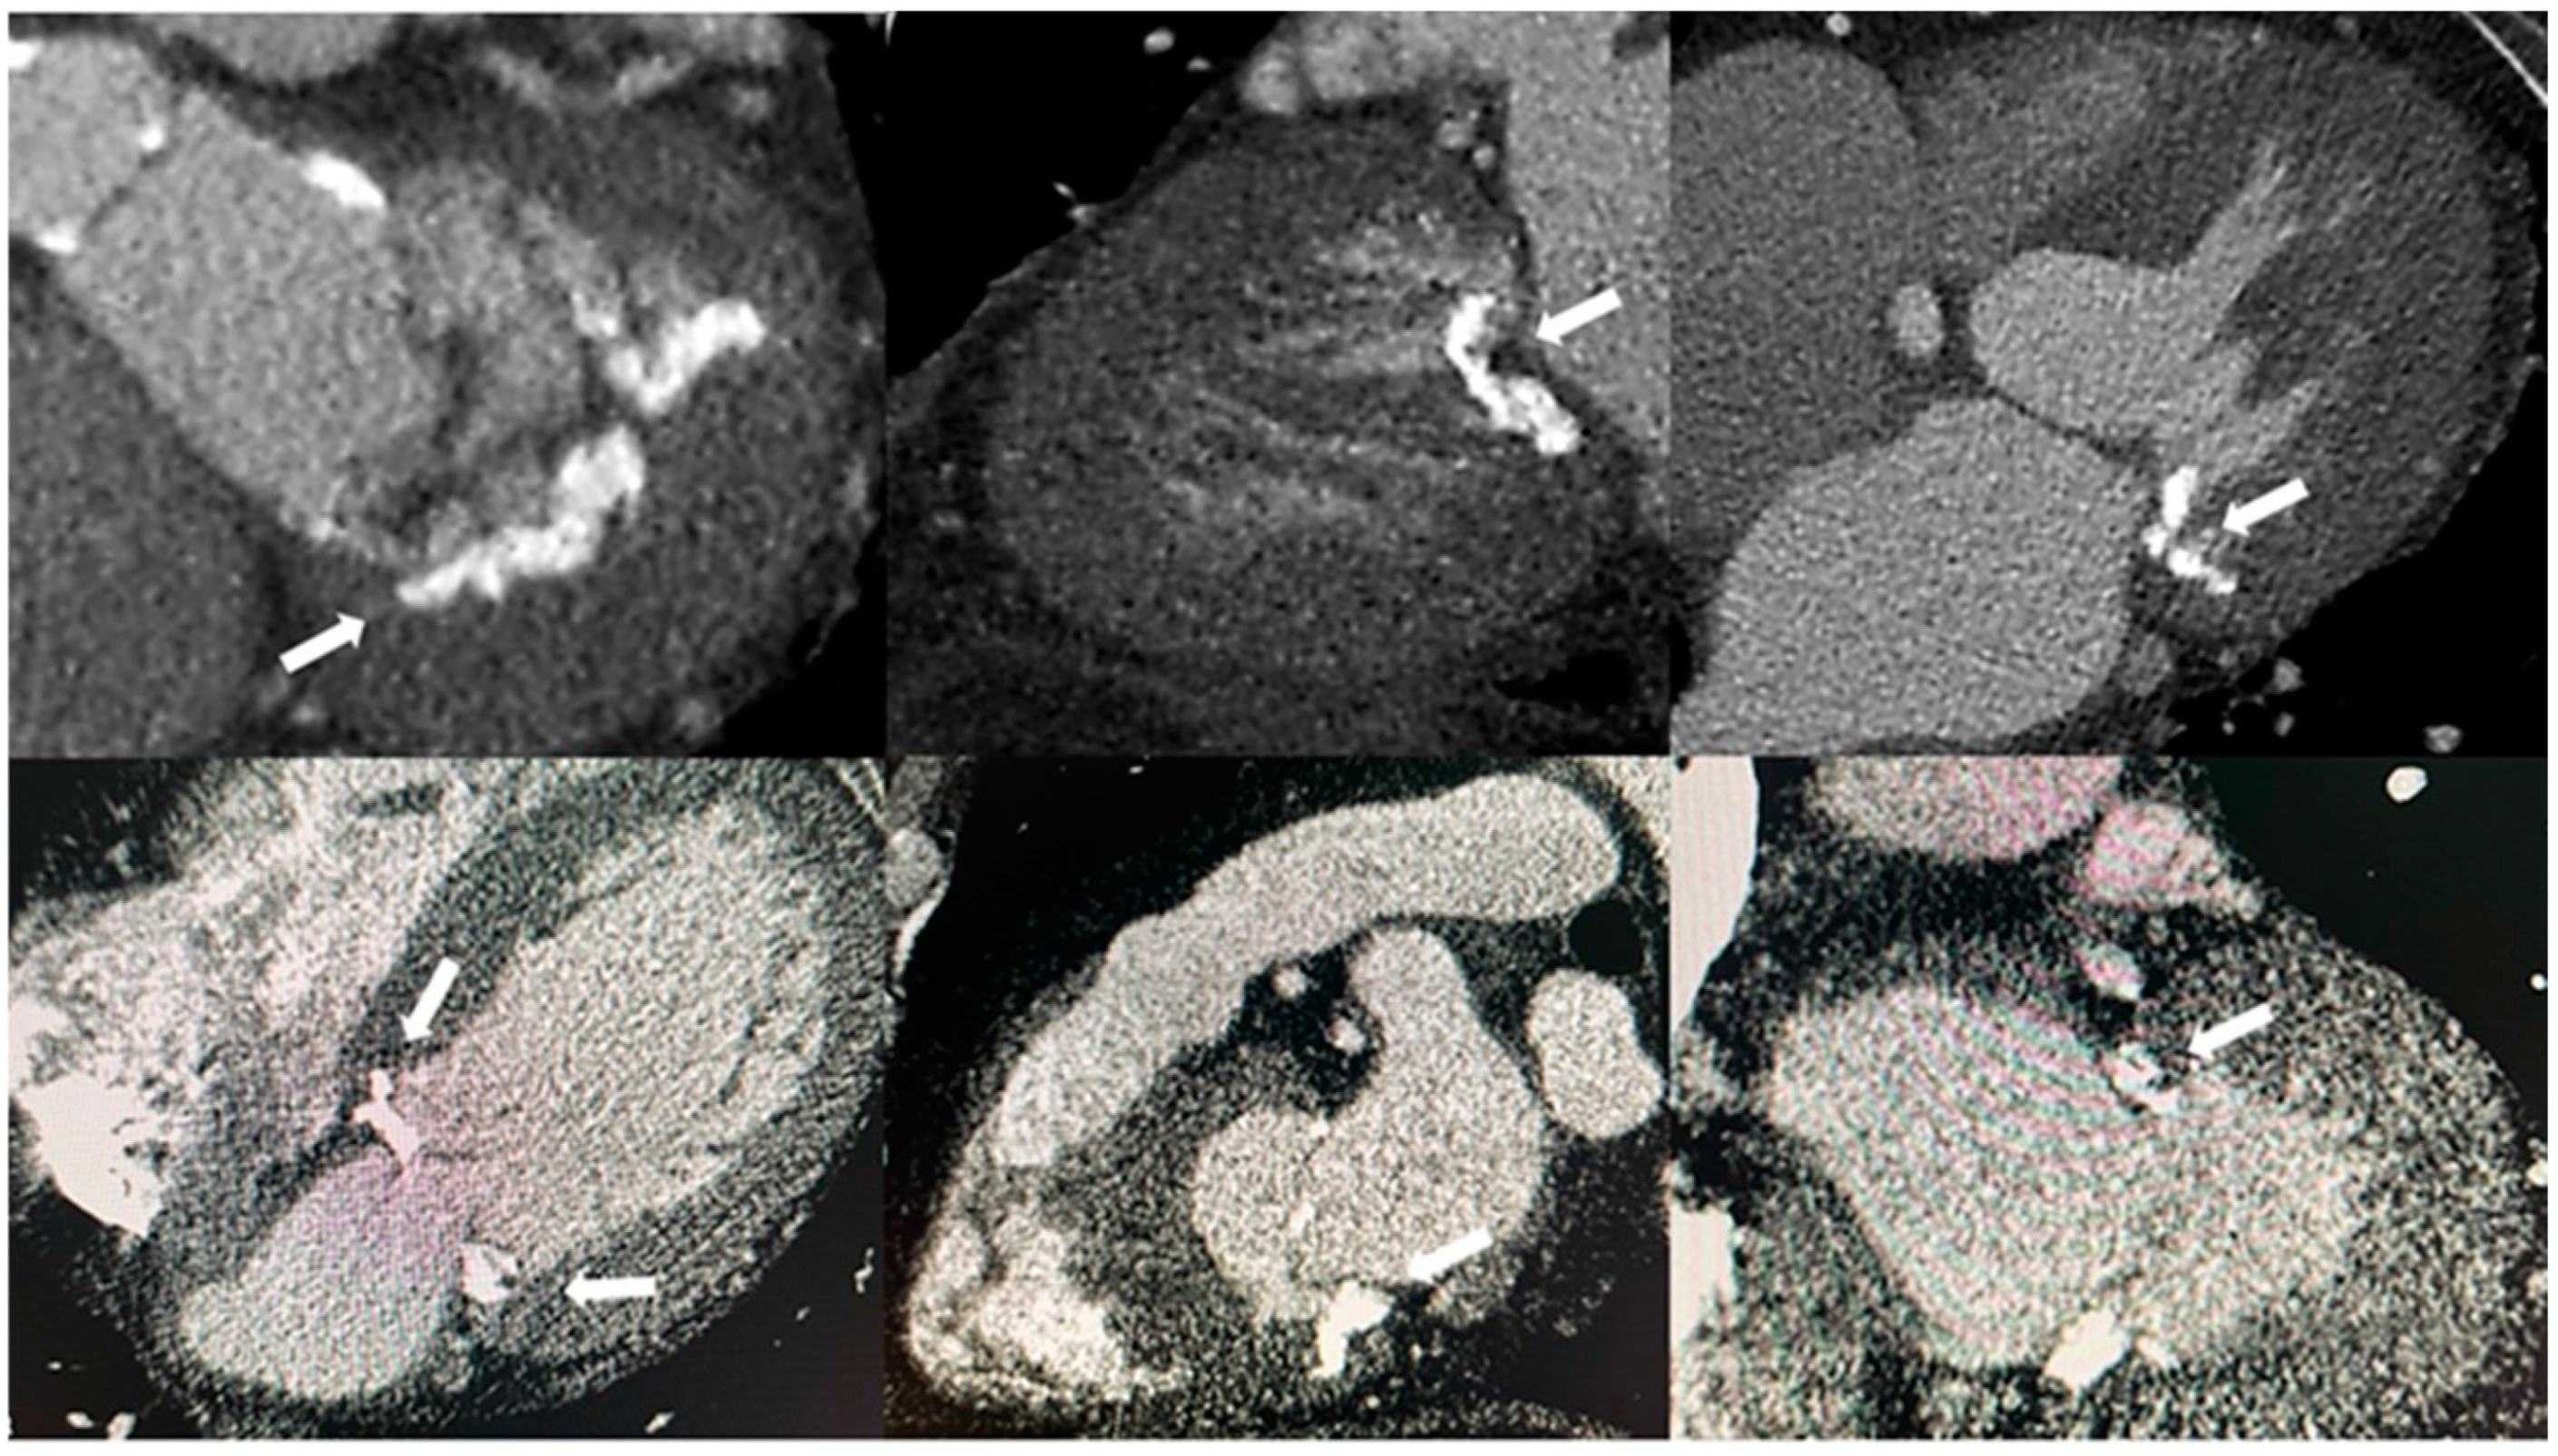

- Higgins, J.; Mayo, J.; Skarsgard, P. Cardiac Computed Tomography Facilitates Operative Planning in Patients With Mitral Calcification. Ann. Thorac. Surg. 2013, 95, e9–e11. [Google Scholar] [CrossRef] [PubMed]

- Guerrero, M.; Wang, D.D.; Pursnani, A.; Eleid, M.; Khalique, O.; Urena, M.; Salinger, M.; Kodali, S.; Kaptzan, T.; Lewis, B.; et al. A Cardiac Computed Tomography–Based Score to Categorize Mitral Annular Calcification Severity and Predict Valve Embolization. JACC Cardiovasc. Imaging 2020, 13, 1945–1957. [Google Scholar] [CrossRef] [PubMed]

- Eberhard, M.; Schönenberger, A.L.N.; Hinzpeter, R.; Euler, A.; Sokolska, J.; Weber, L.; Kuzo, N.; Manka, R.; Kasel, A.M.; Tanner, F.C.; et al. Mitral Annular Calcification in the Elderly—Quantitative Assessment. J. Cardiovasc. Comput. Tomogr. 2021, 15, 161–166. [Google Scholar] [CrossRef]